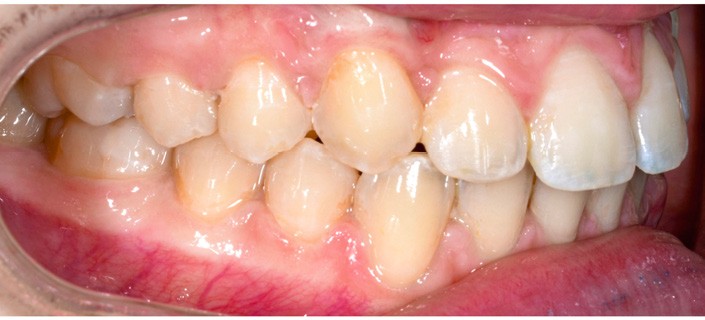

La patiente consulte à l’âge de 9 ans pour la malposition de ses incisives latérales maxillaires. Elle présente une occlusion de Classe I bilatérale sur un schéma normodivergent avec une dysharmonie dento-maxillaire en denture mixte. À l’arcade maxillaire, elle présente une endoalvéolie avec rotations mésiopalatines de 16 et 26.

Sur la radiographie panoramique, on observe une transposition des canines maxillaires en place d’incisives latérales, au contact des racines de 11 et 21.